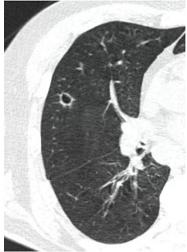

2. Наличие клинических проявлений, указанных в п. 1, в сочетании с характерными изменениями в легких по данным компьютерной томографии (КТ) (см. Приложение 1 настоящих рекомендаций) вне зависимости от результатов однократного лабораторного исследования на наличие РНК SARS-CoV-2 и эпидемиологического анамнеза.

- Изменения при КТ (рентгенографии), типичные для вирусного поражения (объем поражения минимальный или средний; КТ 1-2)

- Изменения в легких при КТ (рентгенографии), типичные для вирусного поражения (объем поражения значительный или субтотальный; КТ 3-4)

- Изменения в легких при КТ (рентгенографии), типичные для вирусного поражения критической степени (объем поражения значительный или субтотальный; КТ 4) или картина ОРДС.

КТ имеет высокую чувствительность в выявлении изменений в легких, характерных для COVID-19. Применение КТ целесообразно для первичной оценки состояния ОГК у пациентов с тяжелыми прогрессирующими формами заболевания, а также для дифференциальной диагностики выявленных изменений и оценки динамики процесса. КТ позволяет выявить характерные изменения в легких у пациентов с COVID-19 еще до появления положительных лабораторных тестов на инфекцию с помощью МАНК. В то же время, КТ выявляет изменения легких у значительного числа пациентов с бессимптомной и легкой формами заболевания, которым не требуется госпитализация. Результаты КТ в этих случаях не влияют на тактику лечения и прогноз заболевания при наличии лабораторного подтверждения COVID-19. Поэтому массовое применение КТ для скрининга асимптомных и легких форм болезни не рекомендуется.